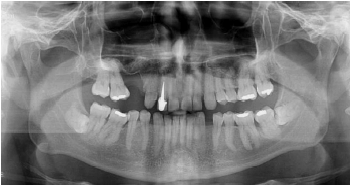

Paciente do sexo masculino, 55 anos de idade, comparece ao consultório odontológico encaminhado pelo ortodontista, sem queixas álgicas. No exame clínico, não foi possível visualizar os dentes 38 e 48, que estavam totalmente recobertos por gengiva e sem sinais de inflamação ou infecção. Na radiografia panorâmica, evidencia-se ambos retidos e impactados, sem sinais sugestivos de patologias associadas. Foi solicitada tomografia computadorizada por feixe cônico e confirmou-se íntimo contato do 48 com canal mandibular. Dentre as seguintes características, assinale a alternativa que apresenta um fator que contraindica a realização da coronectomia no dente 48.